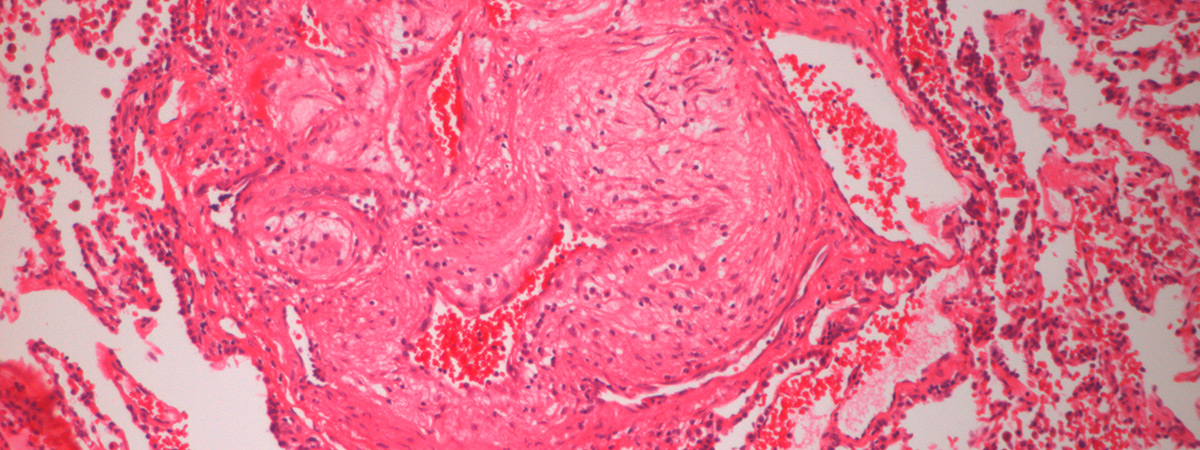

Idiopathic and heritable forms of pulmonary arterial hypertension (PAH) are devastating conditions associated with high morbidity and mortality. The disease is usually diagnosed late by finding a markedly increased pulmonary arterial pressure (increased blood pressure in the arteries of the lungs), the result of progressive narrowing and obliteration of the pulmonary vasculature, which often results in failure of the right ventricle. This disease tends to present in the middle decades of life, with a female predominance.

A major breakthrough in our understanding of the molecular basis of hypertension PAH was the identification of heterozygous germline mutations in the bone morphogenetic protein type II receptor (BMPR-II) in the majority (>70%) of familial cases of the disease and a significant proportion (15-26%) of sporadic cases. Although the presence of mutations in BMPR-II is the greatest risk factor for the development of PAH, it is estimated that only 20% of carriers develop the disease. Additional factors are required for disease manifestation. These may be genetic and/or environmental, though the identity of these factors remains unknown.